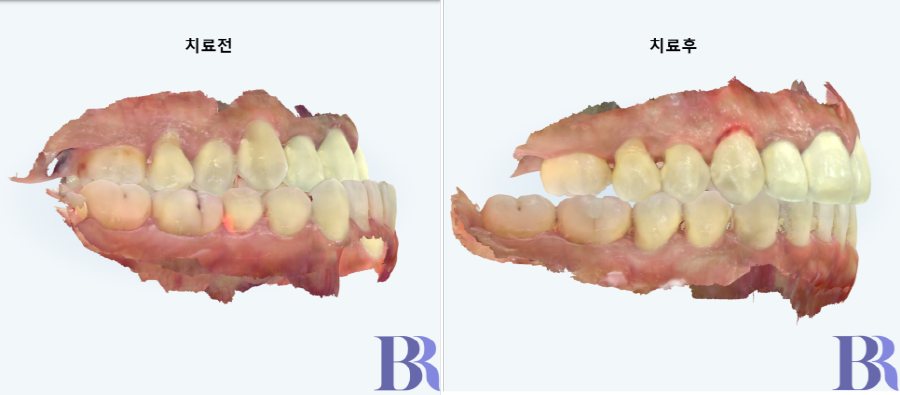

치료전 좌측 모습 : 50년 동안 이렇게 앞니로

무언가 끊어 먹으실 수도 없게 지내셨다.

치료 전후 우측 모습: 반대교합이 훌륭하게 해결

외모의 변화도 빨리 이루고 싶고

교정도 안보이게 하시고 싶은 마음을

충분히 헤아려, 선수술과 인비절라인으로

진행하였는데 결과도 만족스럽고,

그 과정도 환자와 저도 모두 만족하는

치료가 되었습니다.

치료 전후 좌측 모습: 보기에도 아름답지만,

앞니도 잘 사용할 수 있고 어금니도 잘 교합되어 기능적으로 훌륭한 치료가 되었다.